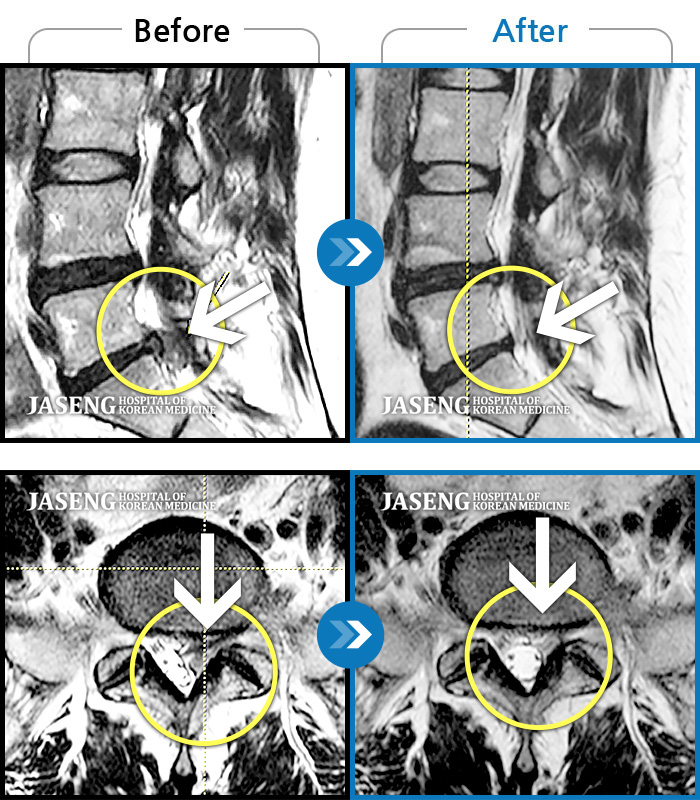

Before

After

환자에게 사전 동의를 받아 동일 조건에서 촬영되었습니다.

개인에 따라 치료 후 부작용이 발생할 수 있으니 의료진과 상담 후 치료를 진행하시기 바랍니다.

반복적 업무 후 시작된 요통 왼쪽다리 방사통과 발가락의 감각저하로 내원